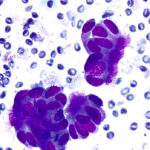

Slide Quality

Our propriety monolayer preparation ensures minimal cellular overlap, giving a clear view of cellular features. Every slide looks expertly done—even without the expertise.